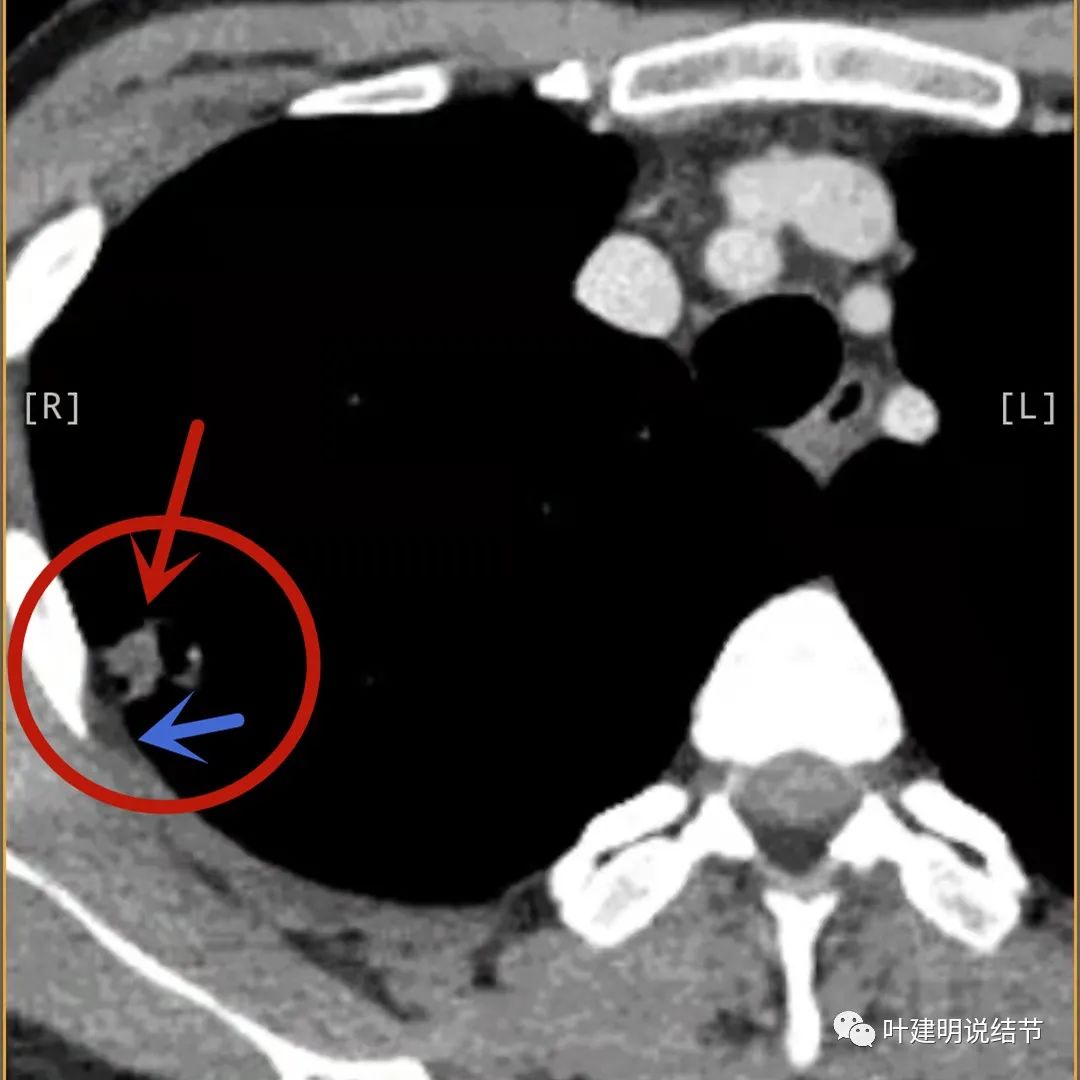

主病灶出现,粉色箭头示病灶密度较高,边上有磨玻璃影,甚淡(砖色箭头)

病灶有空洞(黄色箭头),主病灶边上见条索状高密度影(细红色箭头),邻近胸膜有粘连(蓝色箭头)